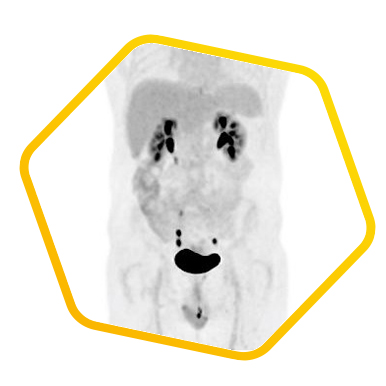

Neuroendocrine Tumor

Dual tracer PET/CT (F-18 FDG and Ga-68 DOTATATE) are used for the metastatic evaluation of neuroendocrine tumor.